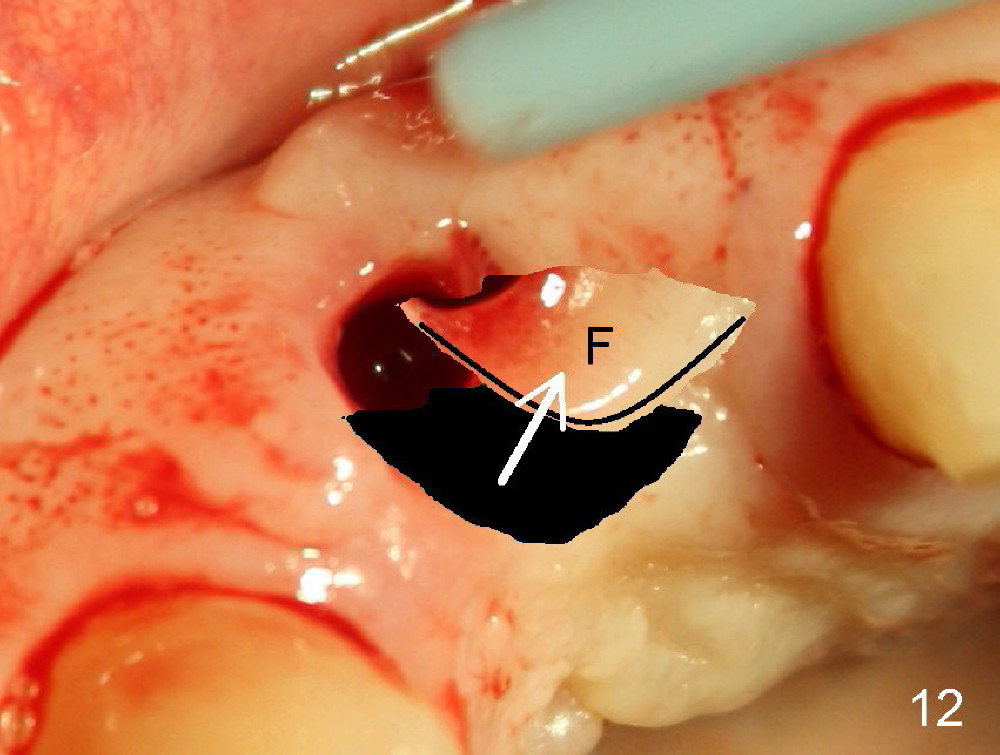

Malpositioned implant in the anterior region is cosmetically unacceptable. Immediate provisional allows us to note the issue immediately. The crown looks too long. Secondly, the provisional is easily dislodged, since the buccal aspect of the angled abutment is over trimmed (Fig.1). The implant (3.8x14 mm), which has been placed 3.5 months, is unexpectedly easily removed by reverse torque (Fig.2). The buccal wall is intact, whereas there seems to be enough bone lingually to place an implant. A small incision is made (Fig.11) so that the gingival tissue can be transferred buccally (Fig.12) and the immediate implant is to be placed palatally (Fig.13 white circle). There is no difficulty forming osteotomy in the palatal wall, followed by inserting 4.5x20 mm tap at the depth of 17 mm (Fig.3,5). But the tap is not palatal enough (Fig.4). By removing more palatal bone, the 4.5x17 implant (Fig.6) appears to be placed palatally enough for restoration (Fig.7; A: abutment; *: buccal gap). The biggest problem is that the palatal flap (Fig.7 arrowheads) cannot be pushed buccally; instead remains palatally. This leads to buccal tissue deficiency (Fig.8). Connective tissue graft is offered, but declined. The patient insists that she has low smile line. Following immediate provisional, mixture of allograft and synthetic graft is placed in the buccal gap (Fig.9). The overbuilt graft is held in place by perio dressing.

If a larger incision were made (Fig.14) and the flap were dissected freely (Fig.15), the buccal tissue deficiency would be less (Fig.16). Follow up is shown 2 3.